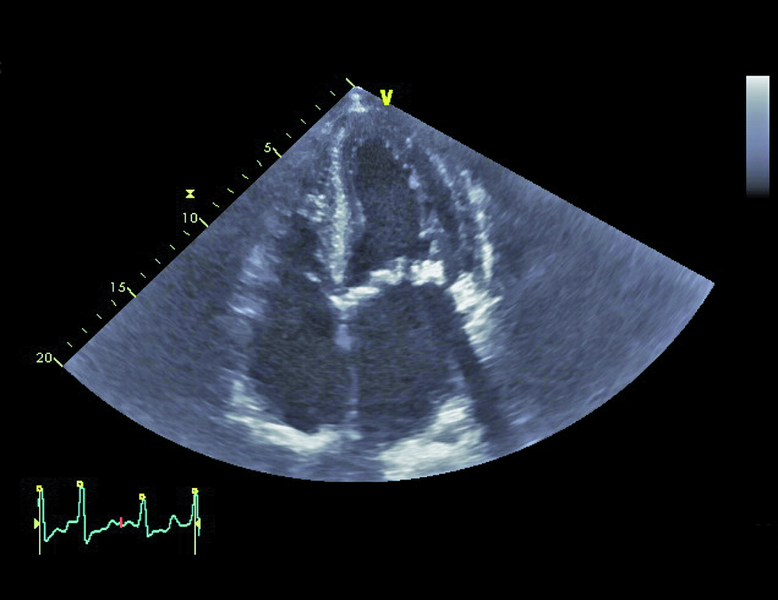

Mężczyzna, lat 79. Jakie patologie można rozpoznać na rycinach?

2. Poszerzenie aorty wstępującej (ryc. 2).

5. Przerost mięśnia lewej komory (ryc. 4, 5).